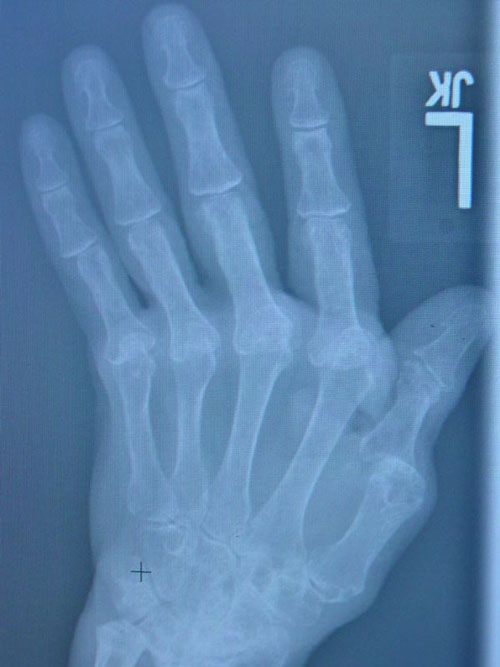

This 62 year old lady presented with a 20 year history of rheumatoid arthritis medically managed by her rheumatologist. Unfortunately, her hand deformities were progressive to the point where many daily activities were hampered. She was understandably concerned about the appearance as well. She underwent replacement arthroplasties of her metacarpophalangeal joints (knuckle joints) using silicone spacer components. This not only improved the function of her hand, but markedly improved the cosmetic appearance as can be seen her.